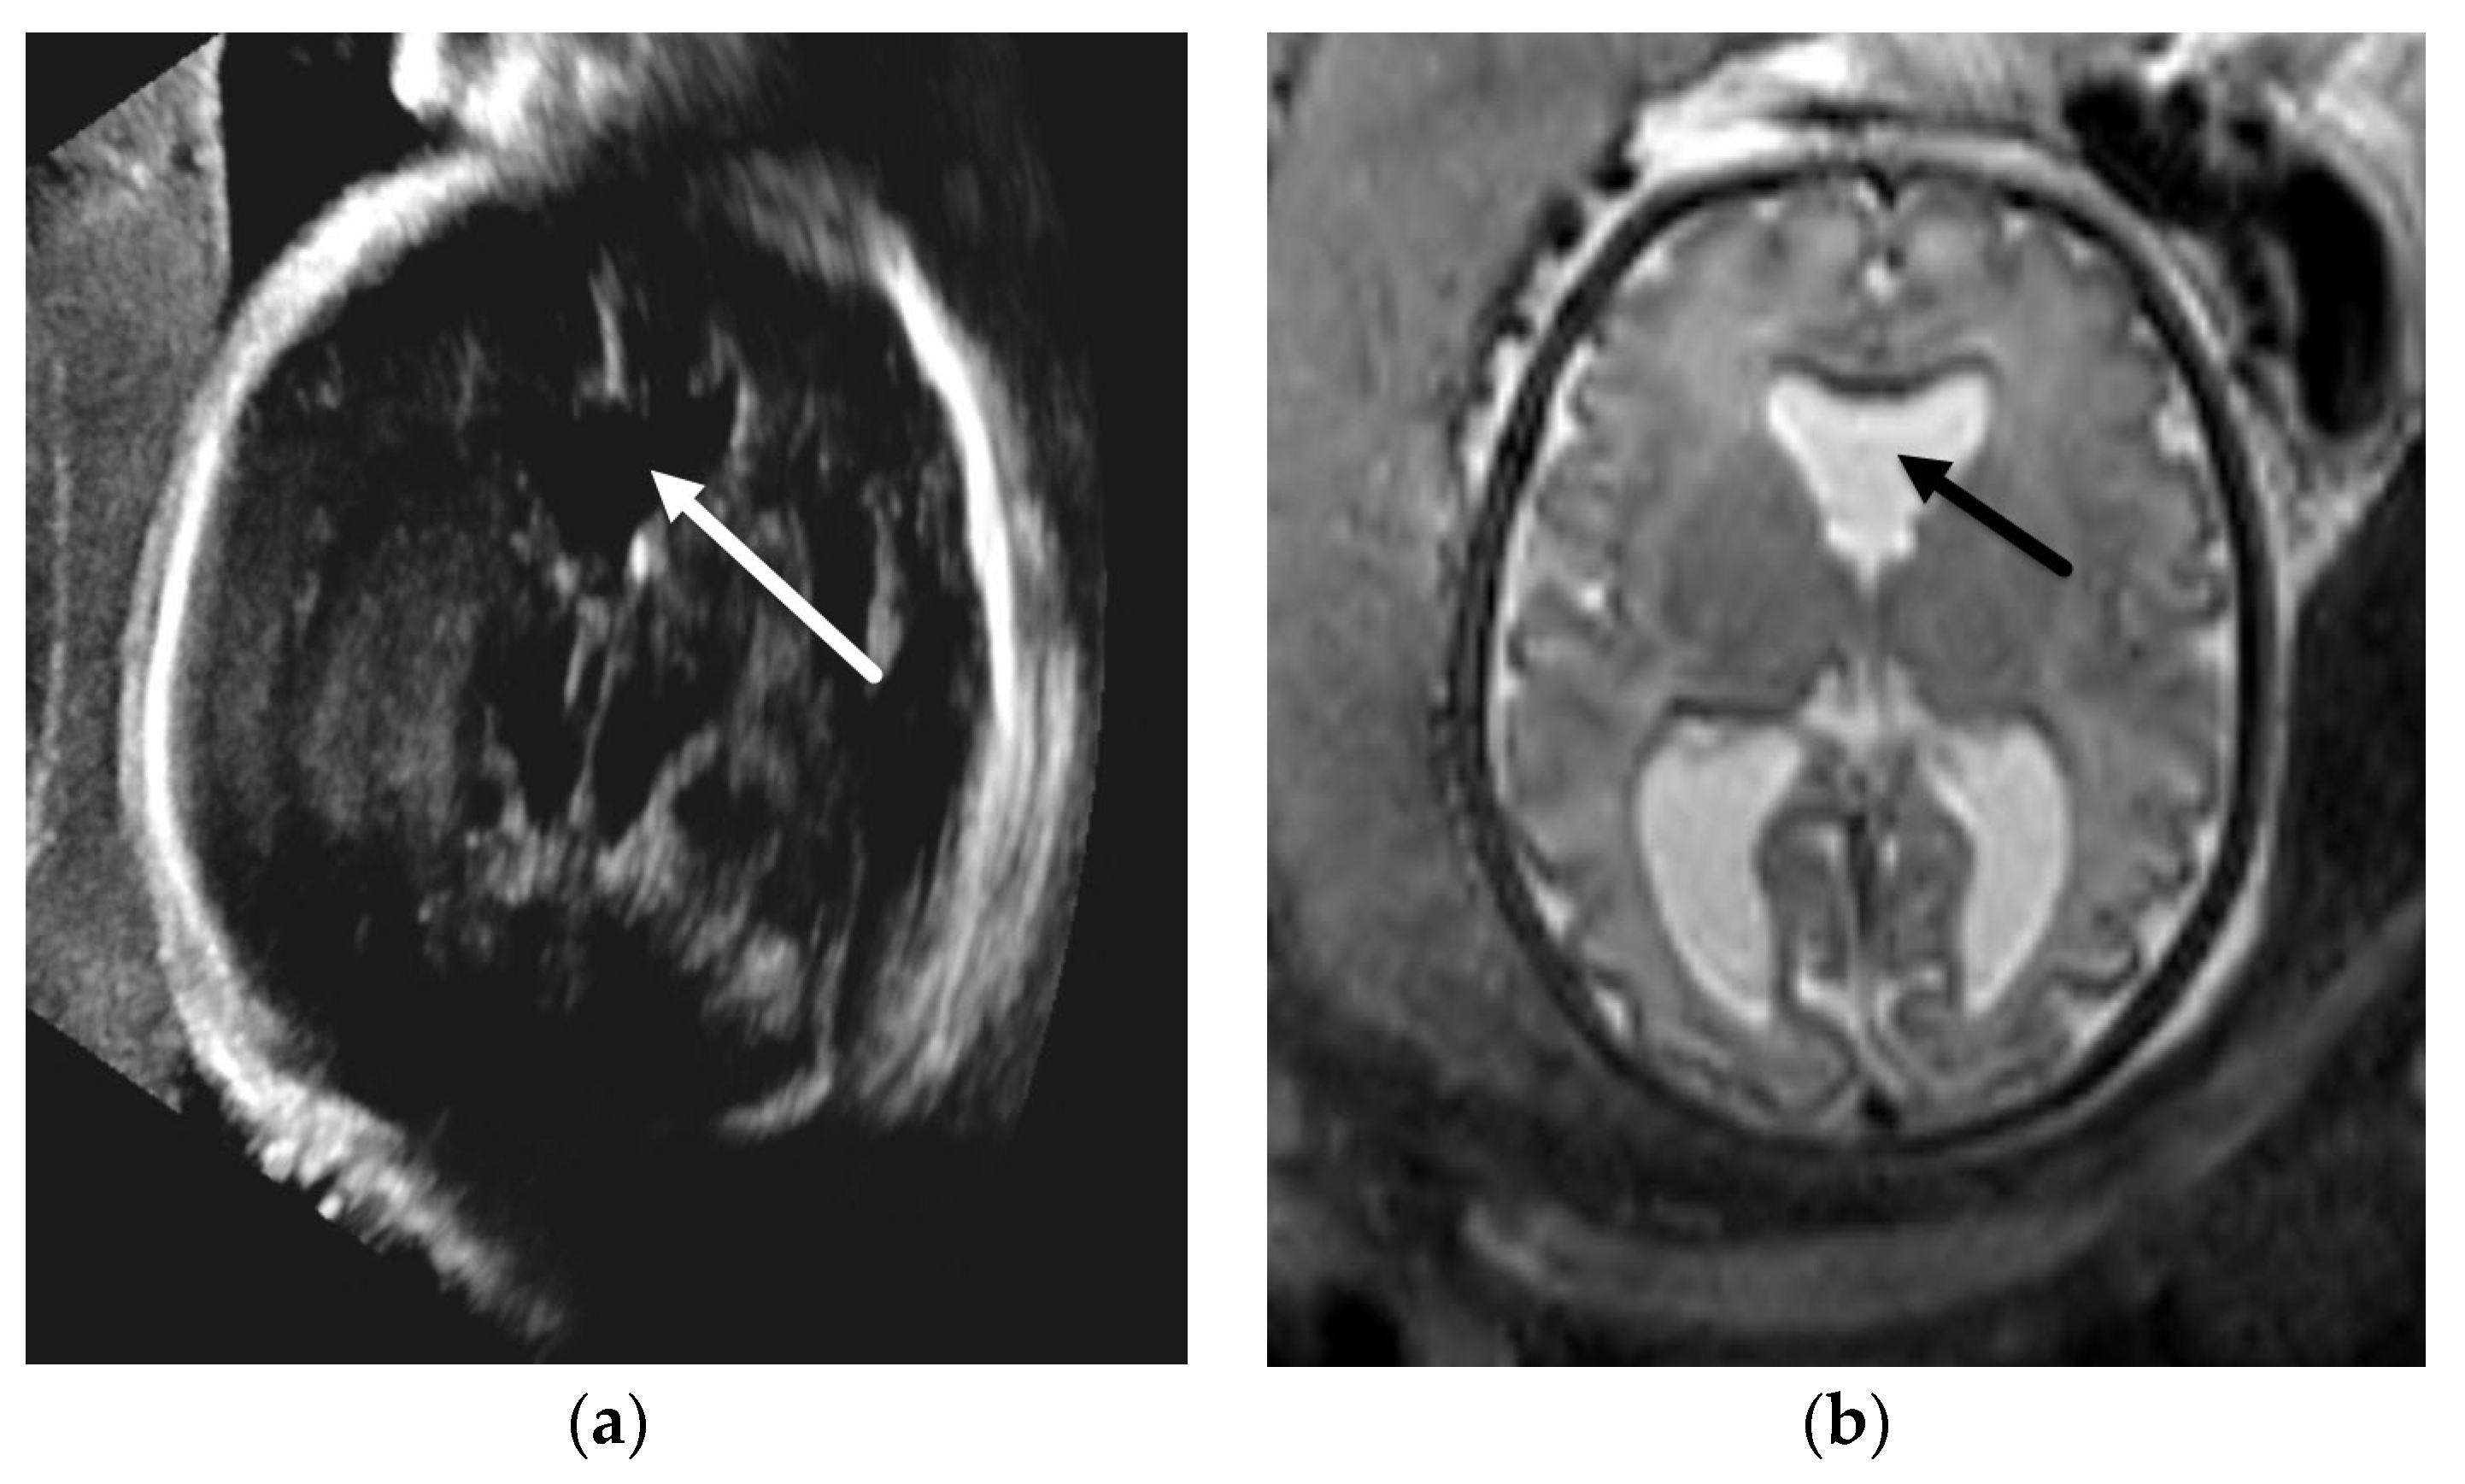

- Epstein, K.N.; Kline-Fath, B.M.; Zhang, B.; Venkatesan, C.; Habli, M.; Dowd, D.; Nagaraj, U.D. Prenatal Evaluation of Intracranial Hemorrhage on Fetal MRI: A Retrospective Review. Am. J. Neuroradiol. 2021, 42, 2222–2228. [Google Scholar] [CrossRef]

- Hayashi, M.; Poretti, A.; Gorra, M.; Farzin, A.; Graham, E.M.; Huisman, T.A.G.M.; Northington, F.J. Prenatal Cerebellar Hemorrhage: Fetal and Postnatal Neuroimaging Findings and Postnatal Outcome. Pediatr Neurol. 2015, 52, 529–534. [Google Scholar] [CrossRef]

- Haines, K.M.; Wang, W.; Pierson, C.R. Cerebellar hemorrhagic injury in premature infants occurs during a vulnerable developmental period and is associated with wider neuropathology. Acta Neuropathol. Commun. 2013, 1, 69. [Google Scholar] [CrossRef] [Green Version]